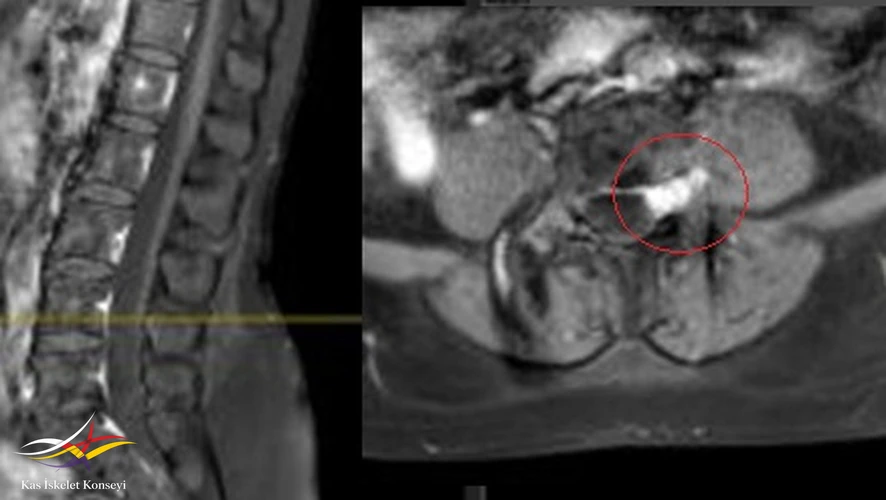

- Lomber MRG: Disklerde yükseklik kaybı veya anüler yırtık yok. L4-5 te solda forameni içinde, kök üzerinde şüpheli bir lezyon lezyon saptanması üzerine yapılan kontrastlı MRG'de lezyonda yoğun ve homojen kontrast tutulumu görüldü ve kitle lehine yorumlandı.

Resim 2. Kontrastlı MRG'de lezyonun yoğun kontrast tuttuğu görülmekte.